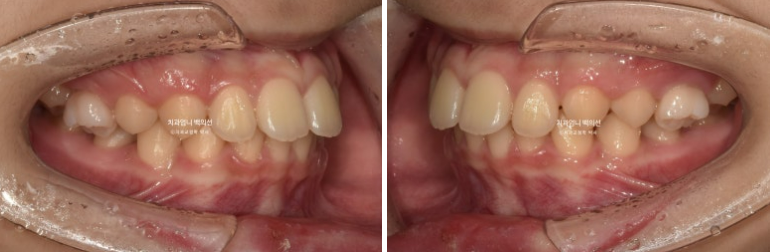

24.03~25.05

앞니 돌출의 개선